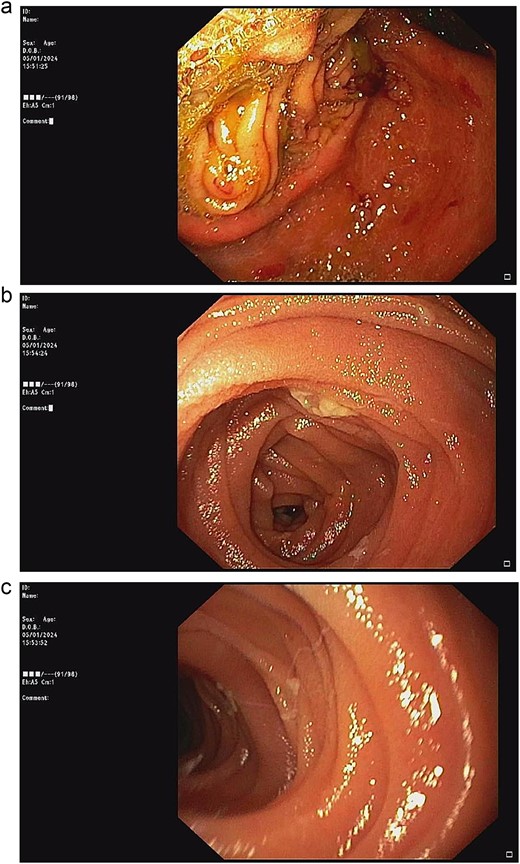

Upper endoscopic findings: (a) patent gastrojejunostomy anastomosis, (b) afferent limb distal to the angulation, (c) efferent limb distal to the angulation.